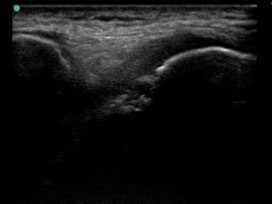

Knee Anterior Trochlear Osteochondral Defect Medial Transverse Image